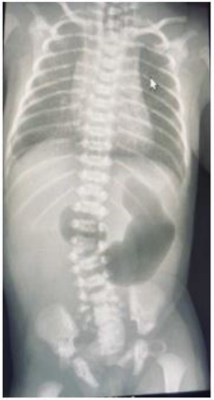

Recém-nascido pré-termo, 35 semanas por trabalho de parto prematuro, em investigação pré-natal de polidrâmnio, após o nascimento foi encaminhado para a UTI neonatal para cuidados intensivos. Evidenciada falha na progressão de sonda orogástrica, confirmado o diagnóstico de atresia de esôfago, compatível com o diagnóstico pré-natal de polidrâmnio. Baseado na radiografia abaixo, a provável malformação do trato gastrointestinal associada neste paciente é: